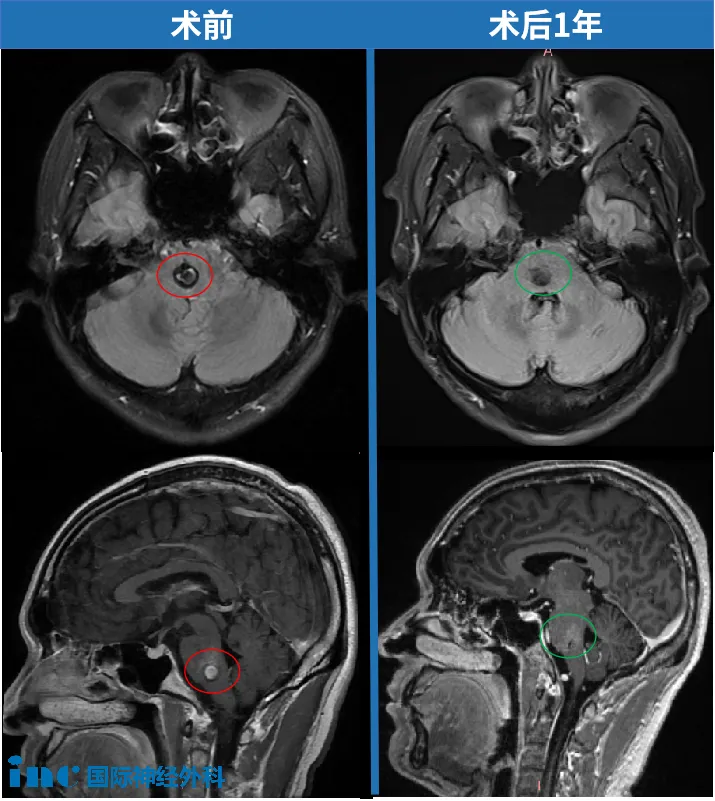

在进一步检查后,他被确诊为脑干桥脑海绵状血管瘤,病灶大小0.8cm。作为从业30年的麻醉医生,他比普通人更清楚脑干手术的风险。但他也明白,海绵状血管瘤不会自行消失。除了手术,几乎没有更好的解决方案。

在他四处咨询的这一个月里,指尖的麻木扩大到手掌、手臂,甚至脚和小腿也开始发麻。多次复查显示,病灶从0.8cm增至1.5×1.2cm。

无奈之下,他也咨询了脑血管科的中医专家,中药、针灸都试了,却收效甚微。两周后再做MRI,出血范围扩大到1.6×1.3cm,DTI检查更是给出了危险信号——丘脑皮质束局部已经受压、破坏。丘脑皮质束的作用是将全身的温度觉、痛觉、触觉、压觉、听觉、视觉整合并传导到大脑皮层。刘先生麻木症状也在不断加重,还出现疼痛。

在国内神经外科团队的配合下,巴特朗菲教授主刀,这场高难度的开颅手术成功了,病灶全切,没有出现偏瘫、面瘫,更没有其他并发症。

如今,距离手术已经过去一年半,刘先生的生活早已回归正轨——开车、骑自行车、正常工作都没问题,只是手指还有些麻木,眼睛重影也没完全消失,“神经恢复本来就慢,不影响生活,我有耐心等。”